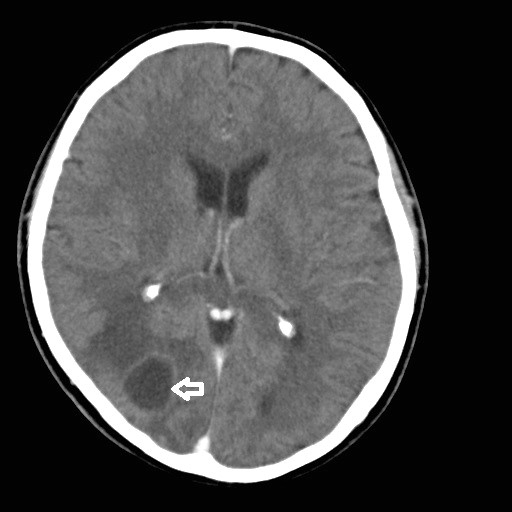

La TC es el método de elección, con una sensibilidad del 95% y especificidad del 85%. En las etapas de cerebritis temprana y tardía, se observa lesión con centro hipodenso, mientras que en las etapas capsular temprana y tardía, se aprecia un patrón en anillo, el cual está dado por un centro hipodenso y una cápsula hiperdensa, que resalta con medio de contraste56 (Figura 3).

En la RM, durante las fases tanto temprana como tardía, las secuencias T1 muestran una imagen hipointensa y en T2 hiperintensa, ambas lesiones con contornos borrosos; en la fase capsular temprana, se observa capsula hiperintensa y un centro hipointenso en T1 mientras que en T2 permanecen ambos elementos hipointensos; finalmente, en la etapa capsular tardía, en T1 la capsula se muestra hiperintensa y el centro hipointenso; por lo contrario, en T2 la capsula es hipointensa y el centro hiperintenso56,61.